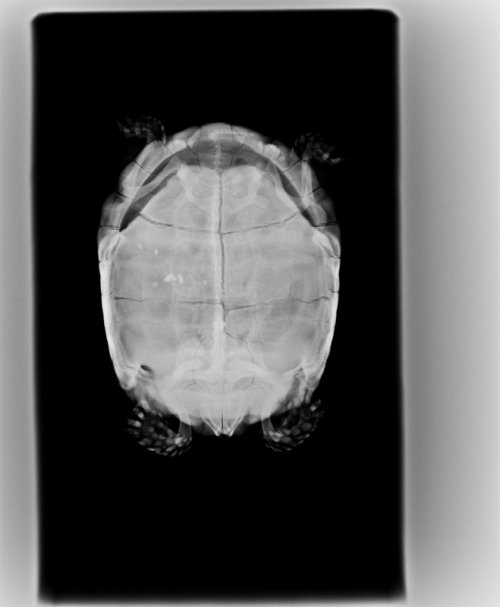

Герпетологов у нас мало, если и есть хороший, то недобратся далеко от дома, я сам тяжело болен, еле встаю с кровати. Связался с ближайшим герпетологом, принял лишь через три дня, только взглянул и сразу высказался, что лечение ничем не поможет. Потом сделал рентген, обсудили рентгенограмму, что лёгкие отекли. Анализы крови сделать не смогли, ибо они отправляют их в Германию, что очень дорого. Дальше проводим такие диалоги уже несколько дней:

Приложу рентгенограммы и фотографии 3-дневной давности.

У Вас нет проекции рентгена, которая бы точно показывала отёк легких или воспаление. Для этого делают кранио-каудальную, а боковую как вспомогательную. Нагревательные коврики запрещены к использованию у черепах. Они плохо чувствуют температуру пластроном, она не может контролировать прогрев на нём, он греет только ближайшие органы, что вредно для черепахи. Я не собираюсь Вам на каждое своё предложение приводить научные статьи и ссылки на ветеринарные статьи, у меня времени на это столько нет и желания что-либо Вам доказывать, потому что Вы не выглядите как человек которому нужна помощь. Я Вам говорю что делать - Вы пререкаетесь и пытаетесь меня убедить, что это не так. Ну не так - ищите там где будет так.

Рентген с боку, черная полоса это лёгкие, их размер 3 раза меньше чем неотекших лёгких.

По рентгену сильная компрессия лёгких, но это не жидкость в них. Легкие это как раз та маленькая светлая область, а затемнение это то, что на них давит - жкт, возможно фолликулы. Черепахе нужны анализ крови, уколы кальция и витаминов, купание и да, вибротерапия, чтобы избавиться от застоя, который давит на лёгкие.

Все препараты нужно колоть в переднюю часть из-за сильных отёков. Прогноз неблагоприятный при отсутствии очного осмотра у адекватного герпетолога, т.к. если это фолликулы, то поможет только операция.

Антибиотики и мочегонное её добьют. Дальше Вам решать что делать с этой информацией.